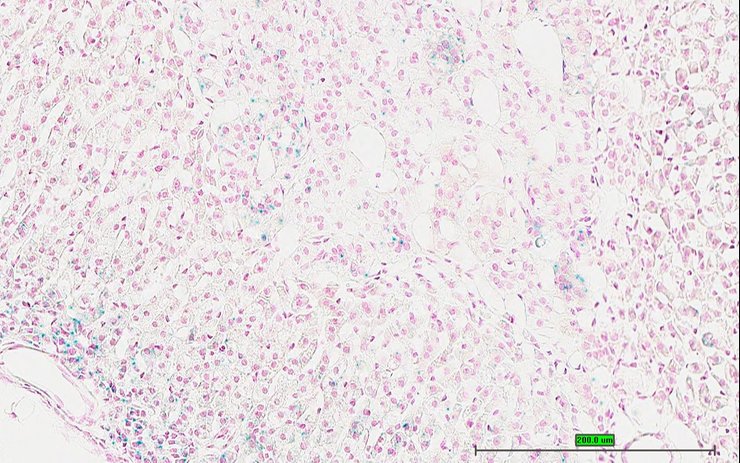

TS28: skin Present UC Davis_1868062

Specimen UC Davis_1868063: postnatal adult; Cnr1tm1.1(KOMP)Vlcg/Cnr1+ (more )

Structure Level Pattern Image Note

TS28: skin Present UC Davis_1868063

Specimen UC Davis_1868064: postnatal adult; Cnr1tm1.1(KOMP)Vlcg/Cnr1+ (more )

TS28: skin Present UC Davis_1868064

Specimen UC Davis_1868065: postnatal adult; Cnr1tm1.1(KOMP)Vlcg/Cnr1+ (more )

TS28: skin Present UC Davis_1868065

TS28: skin Present UC Davis_1868091